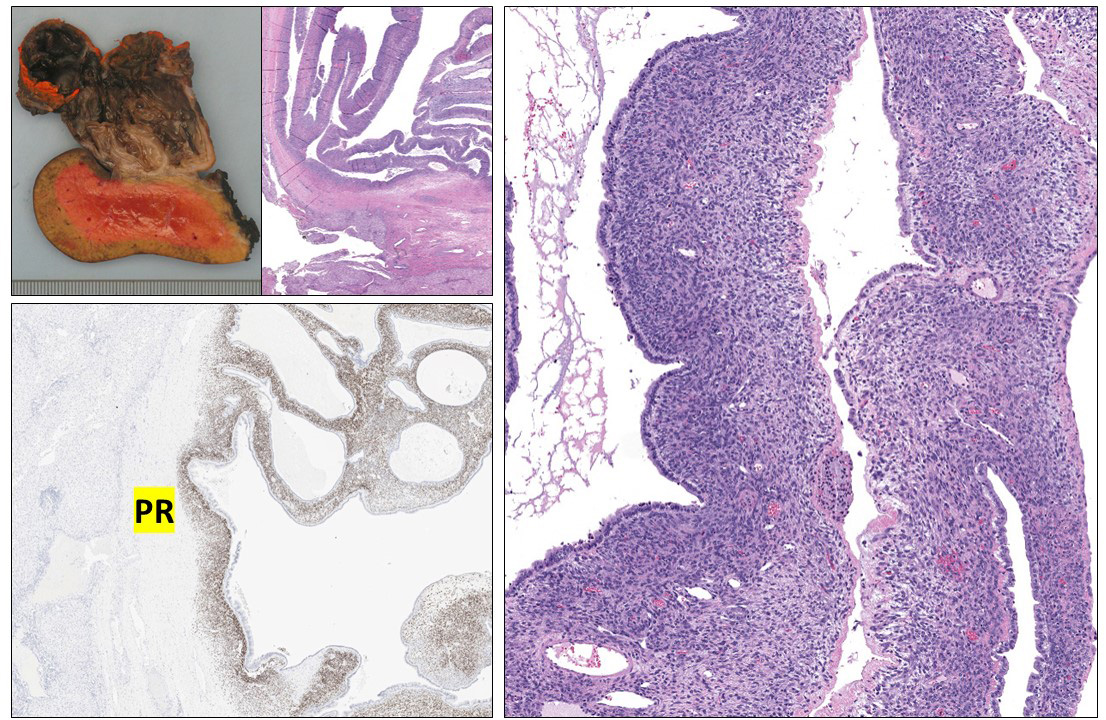

Mucinous cystic neoplasm (#MCN) is not specific to the #pancreas. It is seen in the #liver, too. Ovarian-type stroma is your clue. When in doubt, PR IHC would be helpful. Make sure to check if there is HGD or associated invasive carcinoma. This example only has LGD. @PathTwitter